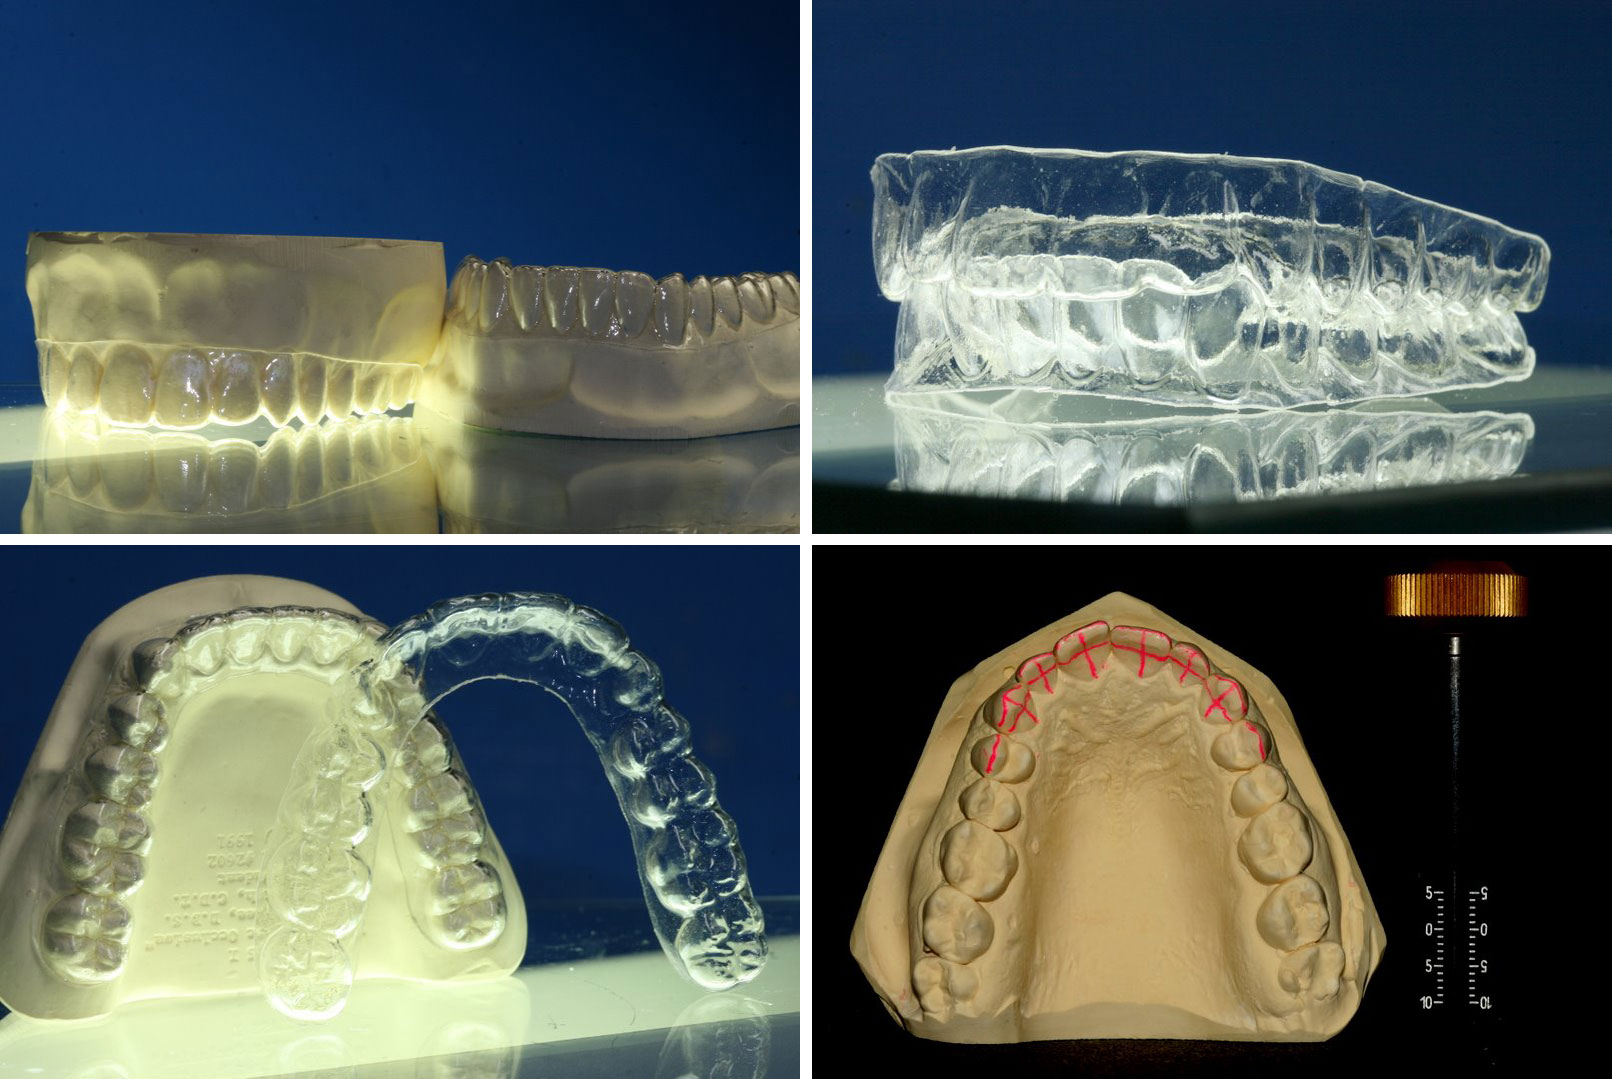

Invisalign, das hat sich die Firma lange Zeit gut bezahlen lassen, durch die erfolgreiche Therapiekonzepte drängten immer mehr Anbieter auf den Markt und heute ist man als Patienten in der Lage zwischen vielen möglichen Anbietern zu wählen. Wir arbeiten mit Invisalign, machen uns aber Schienen auch selber, denn das nötige Equipment wie 3D Drucker und entsprechende Software haben wir im Haus.